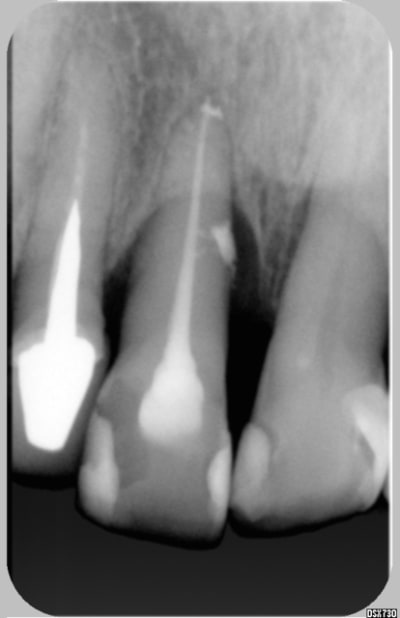

Revue hier, mobilité, nouvelle radio fracture confirmée mais sensibilité -

Sinon à la radio, j'ai plus l'impression d'une lyse apicale que d'une fracture.

je re-poste une radio demain ou l'image est plus nette.Pas la peine de tenter de la soulager pour risquer quoique ce soit, elle n'a plus trop de sensibilité si ce n'est la mobilité de la dent. Donc gêne mécanique, qu'elle gère bien.